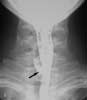

2. Throat pain in a catcher hit with a bat: The lateralradiograph reveals a large, linear collection of gas within theretropharyngeal soft tissues (A, arrow). There are 4 possibleexplanations for gas in a location in which it does notnormally occur:

In this patient, a laryngeal injury is suspected.You order a CT scan of the neck to further investigatethis possibility. An axial image filmed in bone windowsat the level of the thyroid (B) and an axial image filmedin soft tissue windows at the level of the mandible (C)confirm the finding of retropharyngeal gas (arrows).However, no clearly defined track of gas extends fromthe esophagus or trachea. There is also no clear evidenceof hematoma.

You order a Gastrografin swallow. This anteroposteriorprojection of an esophagram at the level of the softtissues of the neck reveals a clear leakage of contrastmaterial from the cervical esophagus at approximatelythe level of the C6 vertebral body (D, arrow).